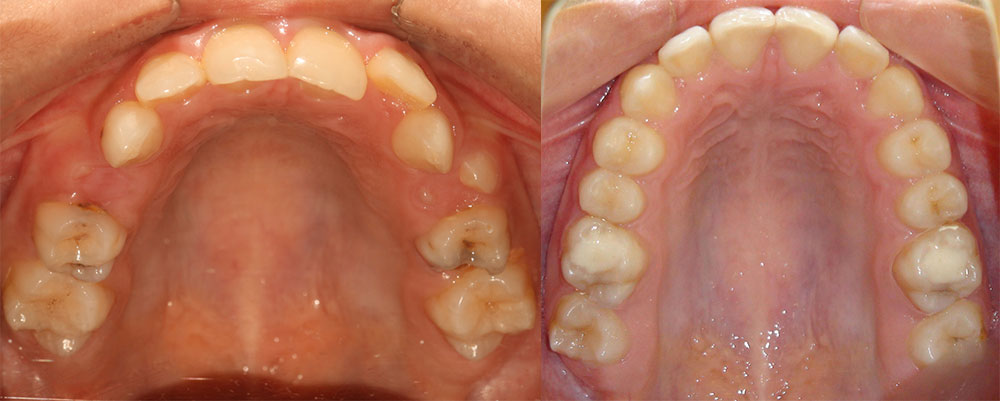

ارتودنسی دندان قبل و بعد، توسط پروفسور جمیلیان

برای دیدن نمونه کارهای ارتودنسی بیشتر می توانید به گالری تصاویر قبل و بعد ارتودنسی مراجعه کنید. در این قسمت تعداد بیشتری از این نمونه کارهای ارتودنسی دندان و فکین را مشاهده خواهید نمود. بسته به ناهنجاری فک و دندان درمان های متفاوتی در نظر گرفته می شود. در اینجا عکس دندان هایی که نیاز به ارتودنسی دارند را مشاهده می کنید. ممکن است بیماری شما نیز شبیه به یکی از این موارد باشد. در این صورت می توانید بهبودی و درمان های موفق را در این قسمت به وضوح مشاهده نمایید.